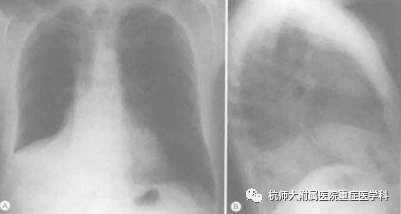

右肺上叶完全不张

不张肺组织导致右侧纵隔旁密度增高

正位胸片上,不张的右肺上叶密度增高,邻近纵隔右侧的胸腔顶部。由于水平裂的抬高导致了不张肺叶下缘轮廓的凹陷,凹陷程度取决于不张的程度,即使不存在阻塞性病变,也可见肺门处有一小的凸出,这是由于肺叶顶端与肺门处静脉和动脉相连所致。侧位片上,水平裂和斜裂几乎均向内上方移位,形成了上部边界不清的楔形致密影。严重肺不张的情况下,水平裂与纵隔趋于平行,外观类似于肺尖区的胸腔积液或正位片上显示为纵隔增宽。

右肺上叶不张也会引起中下叶的代偿性过度膨胀,导致右下肺动脉和右侧主支气管的抬高并变得平缓。血管位置的改变可以在正位片上观察到,但右侧主支气管和下叶支气管的移位在正、侧位片上均较难观察到。